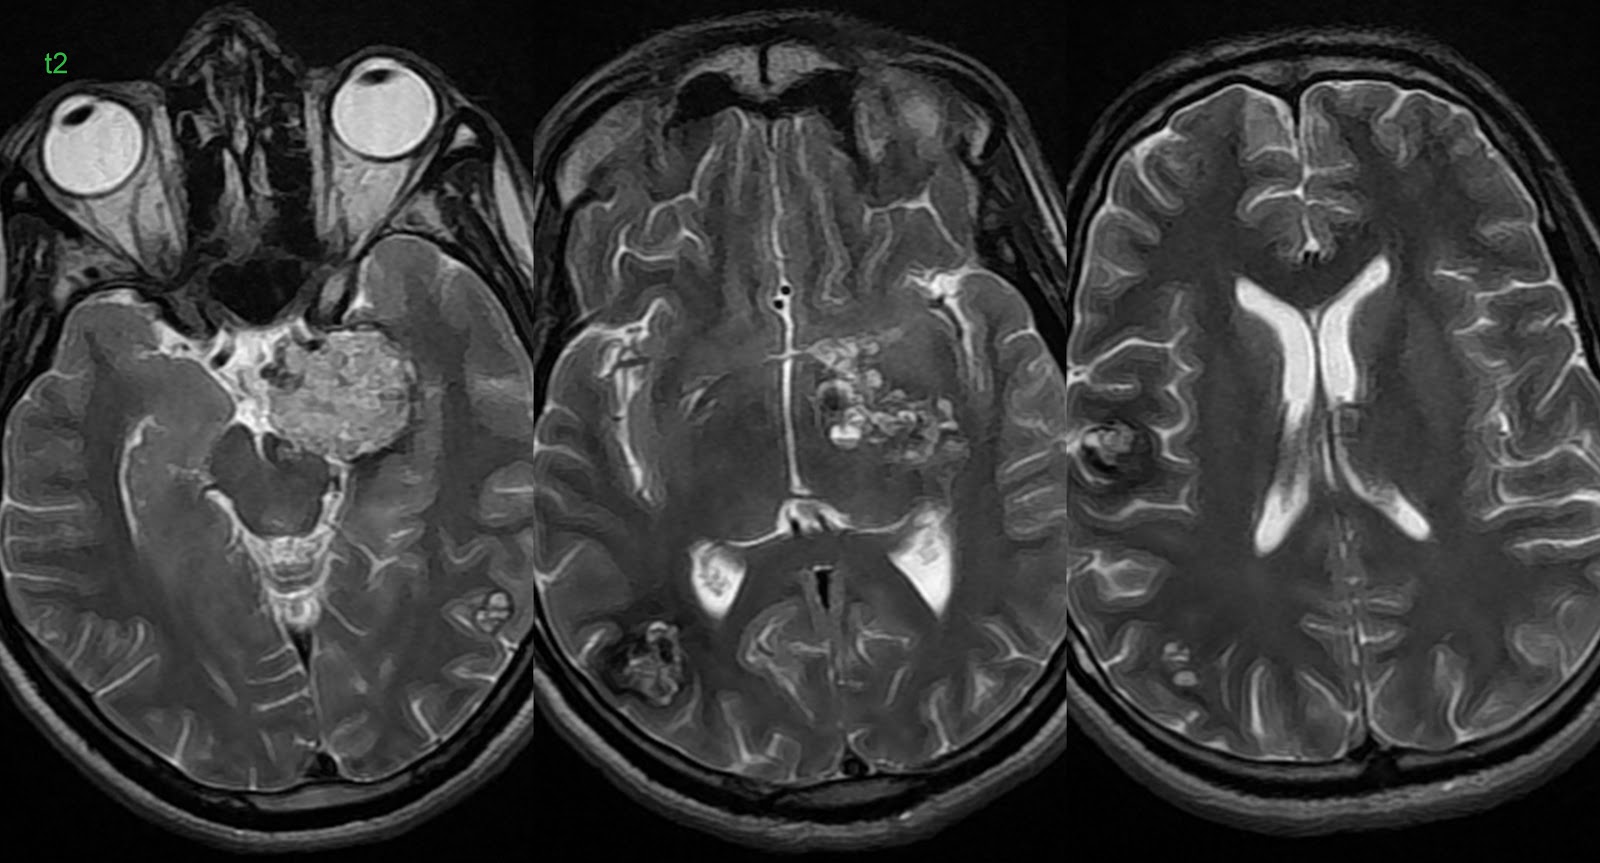

Хроническая ишемия головного мозга и лейкоареоз: симптомы и лечение